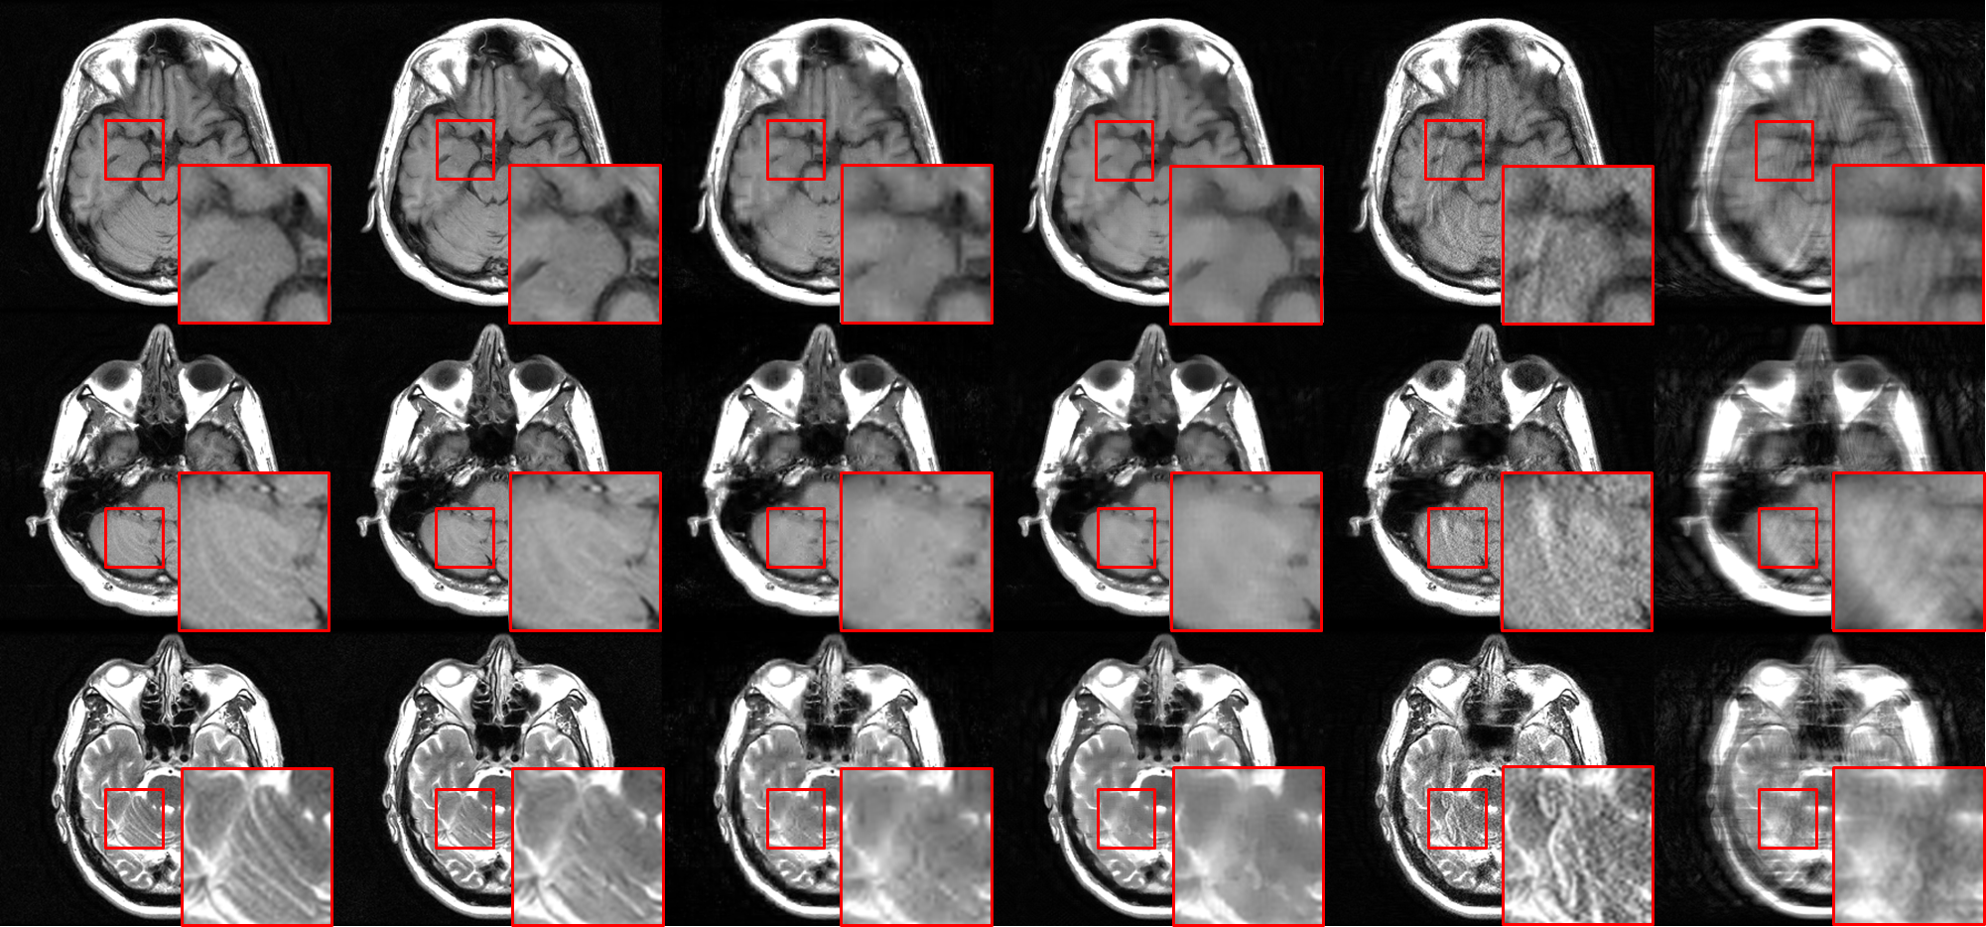

For the sake of completeness, we provide a qualitative comparison of our proposed model to compressed sensing methods using wavelets or TV [4] and to PI [36], as shown in Fig. 11. It can be seen that our proposed method produces higher-quality images than traditional CS and PI methods, both in terms of perceptual quality and reconstruction error.

We compare, in Table III, our cWGAN-AGB with three other models: 1) cWGAN, 2) WGAN, and 3) a baseline DCI-Net for undersampled MRI reconstruction, which optimizes an MSE loss alone without any GAN. All models were evaluated with NMSE and FID on the test set. We found that (a) cWGAN and cWGAN-AGB have better SNR than WGAN, (b) cWGAN-AGB converges much faster than cWGAN or WGAN (Fig. 12), has fewer artifacts, and performs better in both FID and NMSE measures (Table III) and (c) although cWGAN-AGB has higher NMSE than the baseline DCI-Net, it performs better in FID and yields sharper images with more fine details while maintaining a natural image texture. A representative reconstruction can be seen in Fig. 13, where both WGAN and cWGAN models suffer from local inconsistencies with the ground truth image (red arrows). In the same area, our proposed method exhibits a more accurate reconstruction. In addition, Fig. 13 shows a representative reconstruction from the baseline DCI-Net (trained without GAN loss), which exhibits some image blurring.

In Table III, we also compare to baseline architectures, demonstrating the effectiveness of our key new architecture developments: (1) dense connections across all iterations, which strengthen feature propagation, making the network more robust, and (2) a relatively deep architecture of 20 iterations, comprising more than 60 convolutional layers, which brings increased capacity. We compared our generator to (1) an unrolled iterative network, similar to DCI-Net but without dense connections and (2) a 5-iteration DCI-Net with a similar number of learned parameters. Employing dense connections significantly improved accuracy, and the deeper network produced 12% lower mean NMSE than a shallower network with a similar number of learned parameters.